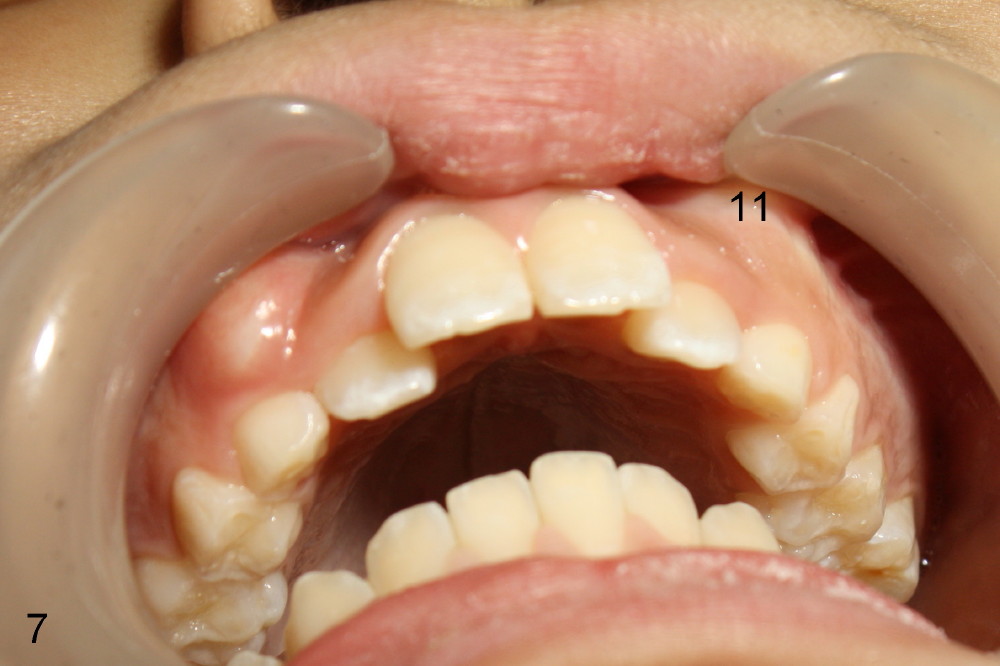

Eight-year-four-month-old boy shows early signs of Class II Division I malocclusion (Fig.2-5).  Panoramic X-ray was taken when he was 5 years 10 months old (Fig.1).

I am afraid that you have seen this patient (Koen) and his mom.  Anyway, he is 10 years 9 months now.  The teeth #6 and 11 appear to be erupting prematurely (prior to #5, and 12) and labially.  I have observed several of this type of cases.  It is apparent that premaxillary protrusion facilitates premature eruption of the upper canines, since there is premature formation of space for them to erupt.  What is your treatment plan or future one?  Thanks.

2nd reply Also Xin in your case of the 8 y.o. boy, I could make the argument that the lingually positioned #7 and #10 may ultimately restrict the lower jaw from growing normally anteriorly.  Their position may very well indeed be in the way.  Check out occlusion from your pictures.  I can explain better in person perhaps.